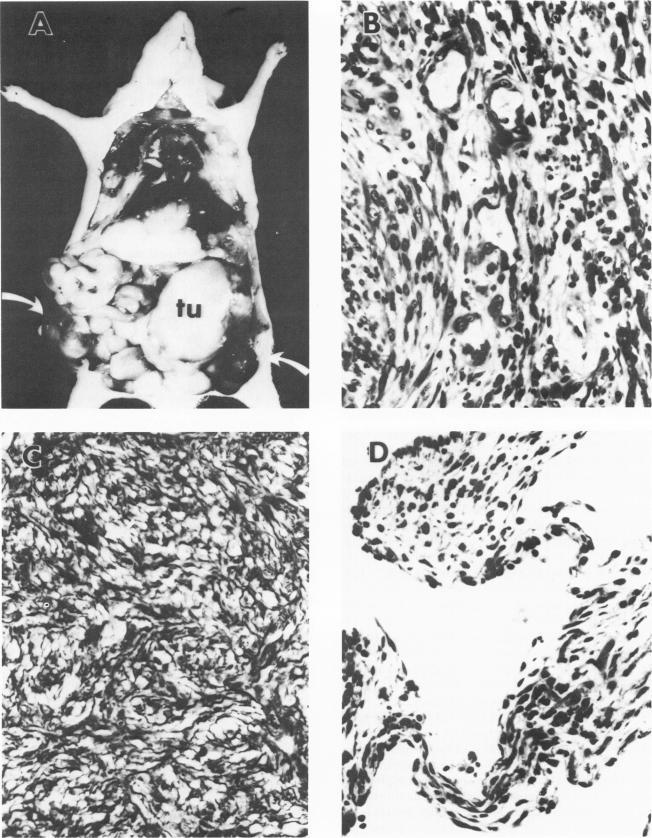

由转染了人类艾滋病卡波西肉瘤DNA的NIH/3T3细胞产生的血管肿瘤。

Vascular tumors produced by NIH/3T3 cells transfected with human AIDS Kaposi's sarcoma DNA.

Patients with the acquired immunodeficiency syndrome (AIDS) have a high incidence of Kaposi's sarcoma. The etiology, histogenesis, and neoplastic nature of this neoplasm have been controversial. We have therefore searched for transforming gene(s) associated with AIDS Kaposi's sarcoma. DNA from an AIDS patient's Kaposi's sarcoma was transfected into NIH 3T3 cells. Control DNA was derived from human fibroblasts or salmon sperm. Kaposi's sarcoma DNA, but not the control DNA, transforms NIH/3T3 cells with a frequency of approximately 0.02 foci per 5 X 10(5) cells/micrograms DNA. The primary and secondary transfectants contain human repetitive DNA sequences. The transfected clones produced hemorrhagic angiosarcomatous neoplasms when implanted in nude mice. The histology of the nude mouse tumors is very similar to human Kaposi's sarcoma. The tumor produced by some transfectants is highly invasive and metastatic in nude mice. No significant homologues of rasN, rasH, rasK, v-sis, v-src and v-fes oncogenes (known to transform NIH/3T3 cells) were identified in the Kaposi's sarcoma DNA-transformed cells. Thus, AIDS Kaposi's sarcoma DNA may contain a distinct transforming gene(s).

获得性免疫缺陷综合征(艾滋病)患者卡波西肉瘤的发病率很高。这种肿瘤的病因、组织发生及肿瘤性质一直存在争议。因此,我们寻找了与艾滋病卡波西肉瘤相关的转化基因。将一名艾滋病患者卡波西肉瘤的DNA转染到NIH 3T3细胞中。对照DNA来源于人成纤维细胞或鲑鱼精子。卡波西肉瘤DNA而非对照DNA能以每5×10⁵个细胞/微克DNA约0.02个集落的频率转化NIH/3T3细胞。原代和二代转染细胞含有人类重复DNA序列。将转染克隆接种到裸鼠体内时会产生出血性血管肉瘤肿瘤。裸鼠肿瘤的组织学与人类卡波西肉瘤非常相似。一些转染细胞产生的肿瘤在裸鼠中具有高度侵袭性和转移性。在卡波西肉瘤DNA转化的细胞中未鉴定出rasN、rasH、rasK、v - sis、v - src和v - fes癌基因(已知可转化NIH/3T3细胞)的明显同源物。因此,艾滋病卡波西肉瘤DNA可能含有一种独特的转化基因。